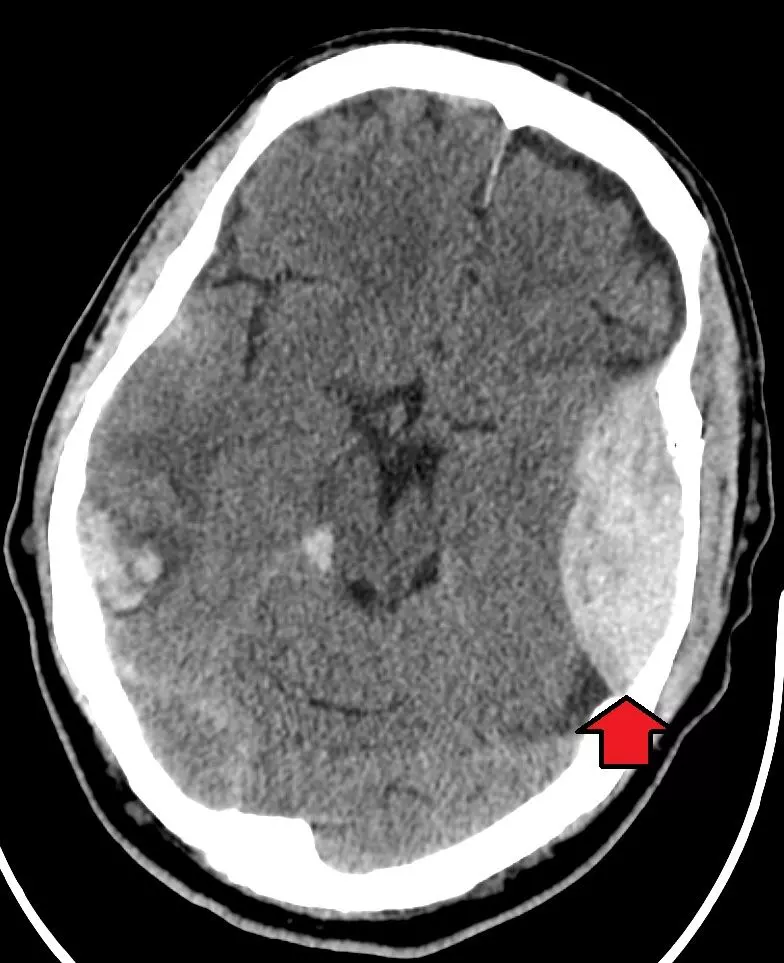

An extradural haemorrhage arises from one of the meningeal arteries, particularly the middle meningeal artery. Blood accumulates between the periosteal dura and inner table of bone. This bleed is confined to the suture lines. Its CT appearance is a biconvex (lentiform) area of hyperdensity.

Image - Axial head CT showing an extradural haemorrhage (indicated by the red arrow)

A subdural haemorrhage arises from the bridging veins. Blood accumulates within the subdural space. The risk of subdural haemorrhage increases in the elderly due to cerebral atrophy, which increases the tension of the bridging veins, making them more fragile. Subdural bleeds can be acute or chronic. On CT these bleeds are crescent-shaped - acute bleeds appear hyperdense whereas chronic bleeds appear hypodense.

Image - Axial head CT showing an acute subdural haematoma (indicated by the red arrow)